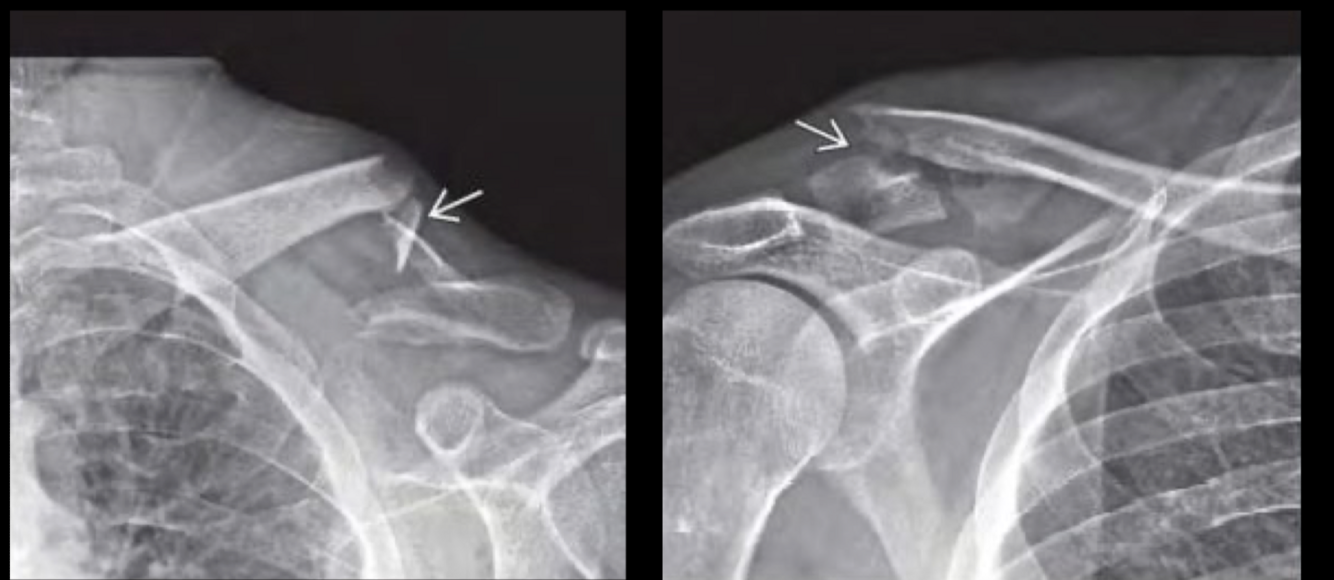

RX fx clavicula

multifragmentaria cabalgada